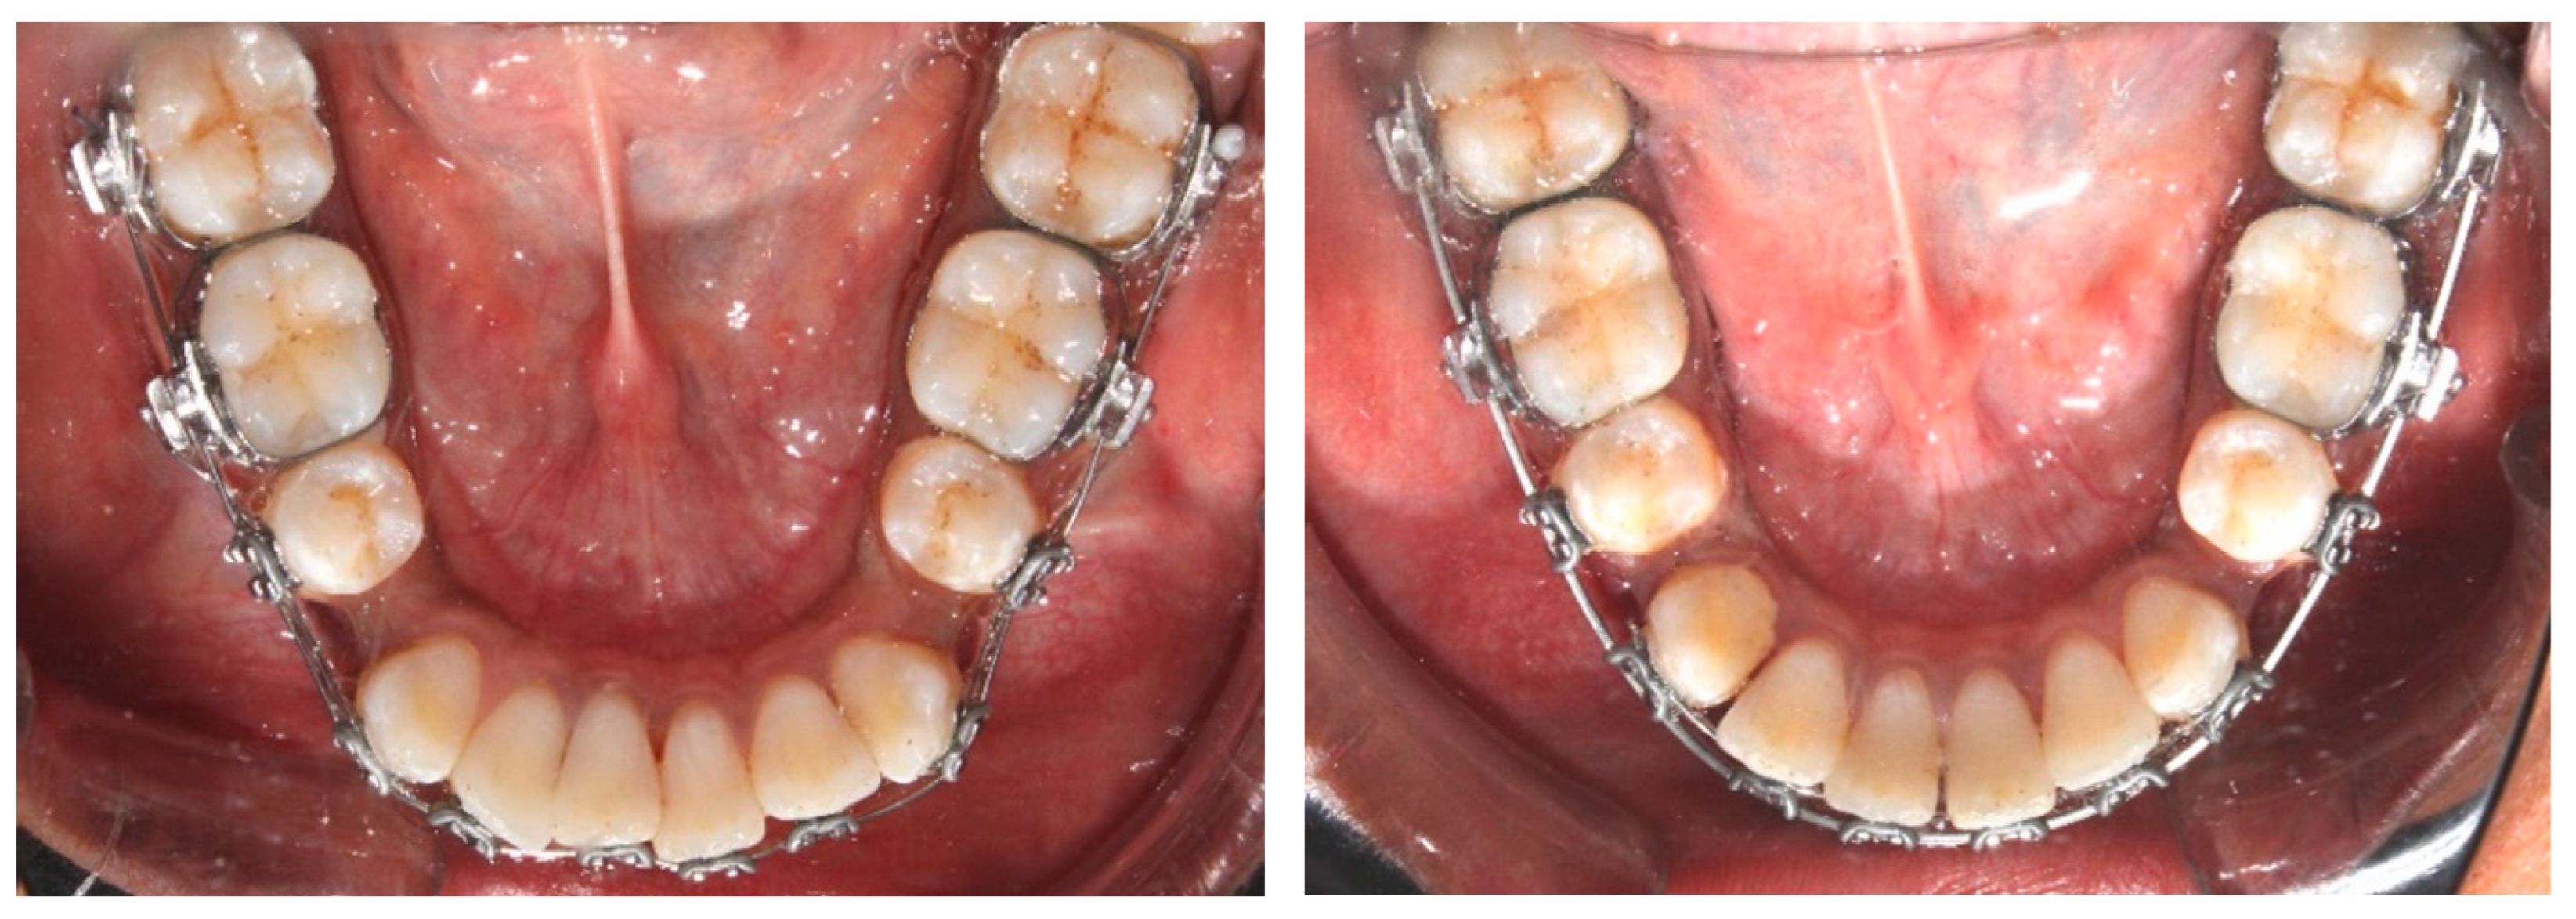

2.4. Orthodontic Procedure